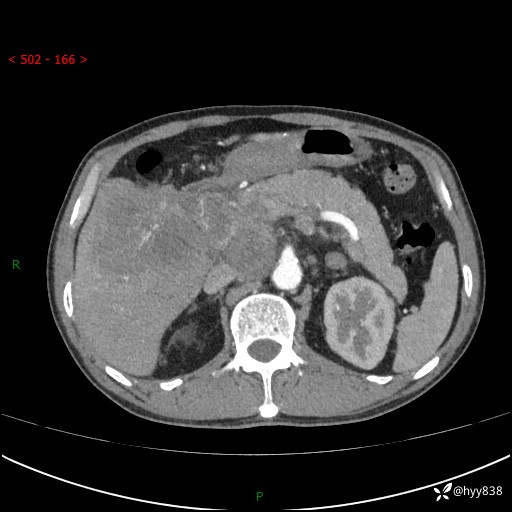

上腹部CT平扫+增强(两期)